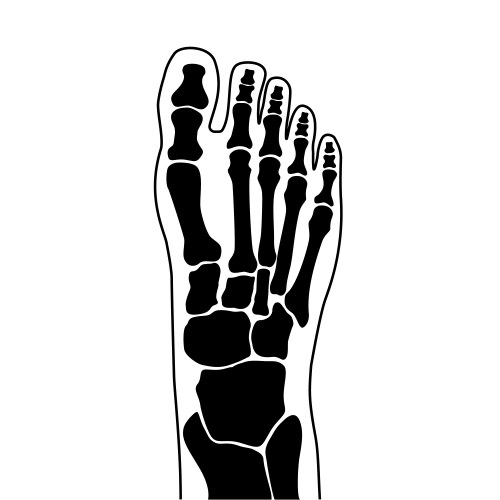

- Running

- Ankle

- Anatomy

- Sprain

- Skeletal

- Illustration

- Injury

- Medical

- Science

- Anatomical

- Arthritis

- Biology

- Bone

- Diagnosis

- Foot

- Graphic

- Health

- Human

- Inflammation

- Joint

- Leg

- Metatarsal

- Pain

- Skeleton

- Therapy

- Walk

- Ache

- Athlete

- Bones

- Condition

- Exam

- Injured

- Lateral

- Painful

- Plantar

- Procedure

- Structure

- Symptoms

- Talus

- Toe

- Transparent